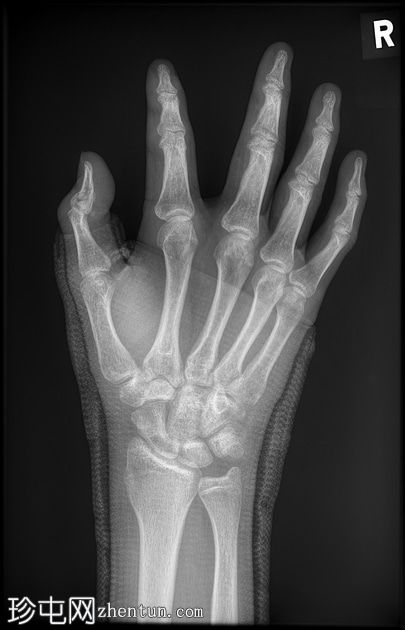

正面片

玻璃纤维拇指人字形石膏固定。

舟骨腰部骨折合并骨折。

第一近节指骨背侧基底部急性关节内骨折。

这位患者很不幸——舟骨骨折几乎已经痊愈,却因摔倒导致拇指远端指骨再次骨折。当然,拇指人字形石膏固定并没有起到作用,反而可能由于近节关节活动范围减小而导致撕脱性骨折。